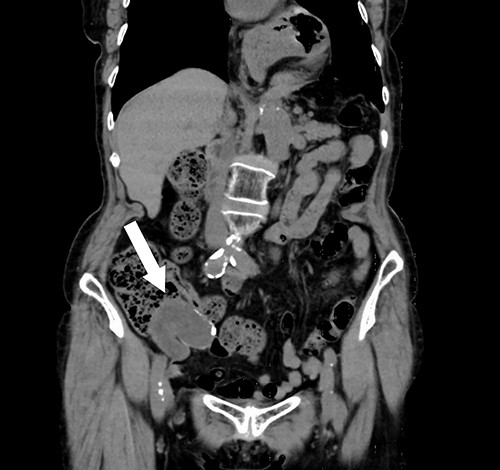

A 74-year-old female with hypertension, hyperlipidemia and hyperuricemia had a colonoscopy as a screening examination. The colonoscopy revealed an extrinsic compression with ulceration located at the cecum (Fig. 1). A multidetector computed tomography (CT) identified a low-attenuation distorted cystic lesion with focal calcification in the anatomic region of the right iliac fossa, measuring 6.1 × 5.0 × 3.7 cm (Fig. 2). Findings from the routine laboratory examinations were unremarkable, and all tumor markers were within normal range. The patient was scheduled for ileocecal resection with lymph node dissection due to the possibility of malignancy, such as appendiceal mucinous adenocarcinoma, because of the large and distorted tumor. Contrast-enhanced CT was conducted for further assessment of the findings, and we found that the cystic lesion was dramatically shrinking. It seemed improbable that rupture of the tumor had happened since no findings implied the spread of mucinous components, such as ascites or mucinous peritoneal nodules on CT. It was considered that the mucinous content was spontaneously drained from the root of the appendix to the cecum. However, the enhanced and distorted lesion with focal calcification, suggesting malignancy, had remained in concordance with the base of appendix (2.7 × 2.1 × 1.9 cm) (Fig. 3). Therefore, ileocecal resection was performed as planned, and laparoscopic procedure was selected due to the unlikelihood of the tumor rupturing. The base of appendix was distended and there were no obvious peritoneal anomalies upon visualization of the abdomen (Fig. 4). The specimen was handled with care and there was no spillage of cystic contents. The post-operative course was uneventful, and the patient was discharged on post-operative day 8.

Screen capture of the appendiceal tumor during the surgical laparoscopic procedure (white arrow: cecum, black arrow: distended appendix).